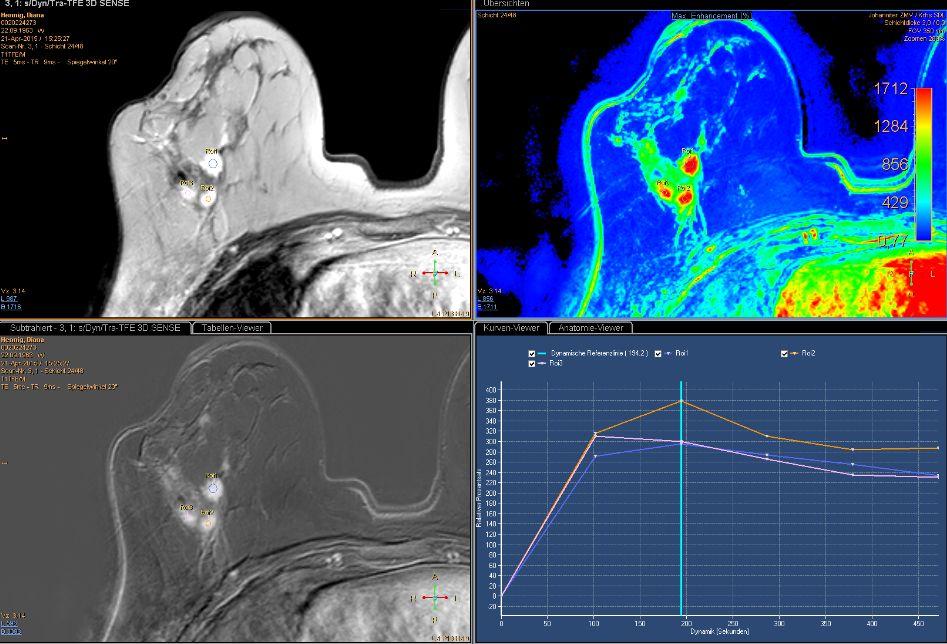

MR im eThrive HR tra sense - Modus: Deutlich Darstellung einen 40mm großen Tumors.

Schnelle Anflutung und langsames Wash-Out sprechen für Malignität.